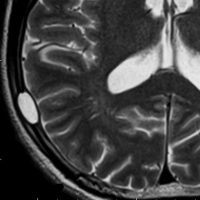

脳のLCH(ガドリニウム増強されるタイプ)

- 左の写真は,両側の側頭葉内側(黄色の矢印)と視床下部(赤)に同時にできたLCHです

- このように脳のLCHは近寄った場所に多発するように散在性に発生することがあります

- まれには,前頭葉全域にガドリニウム増強病変が生じて,悪性グリオーマと間違うようなものもあります

- これを単発病変とするのか1臓器の多発病変とするのかはわかりません

- 左の写真は3ヶ月後のものですが,なにも治療しないで自然に病巣は消失してしまいました(自然寛解)

- しかし,脳のLCHは脳組織を破壊して広がりますから,病像が消えても症状は後遺症として残ることが多いです

- ですから,脳病変が発見されたら正確に診断して治療を行った方がいいでしょう